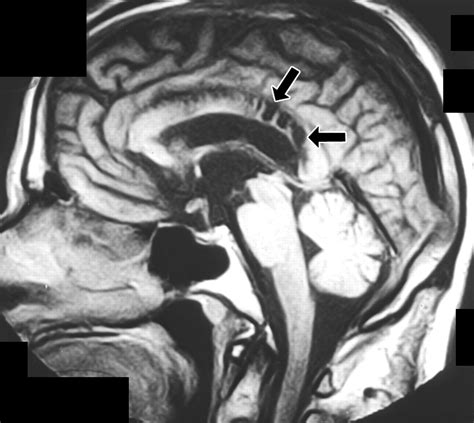

Due to its high concentration of neural pathways, the splenium of corpus callosum is a frequent area of interest in neuroradiology. Magnetic Resonance Imaging (MRI) is the gold standard for evaluating this region. Changes in the integrity of the splenium can be a marker for a variety of neurological conditions, ranging from developmental disorders to acute inflammatory processes.

When clinicians observe signal abnormalities in the splenium, they often look for what is termed "reversible splenial lesion syndrome" (RESLES). This condition often presents with acute onset of symptoms such as confusion, seizures, or vision changes, but interestingly, the lesions often resolve over time without permanent damage. This highlights the unique vulnerability and resiliency of the splenium to metabolic and inflammatory stressors.